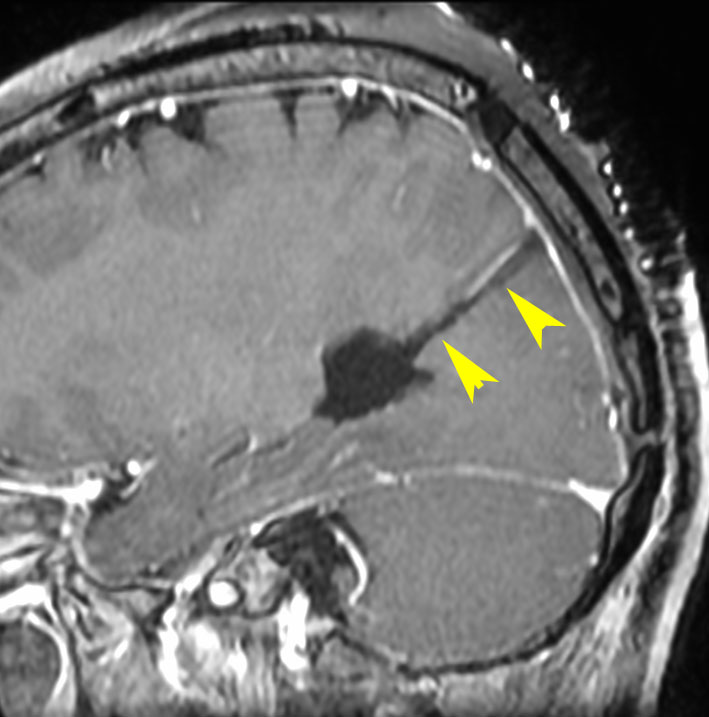

上矢状洞髄膜腫 superior sagittal sinus meningioma

上矢状洞を埋め尽くすように増大して,頭蓋骨浸潤が著しい髄膜腫ですが,ごく軽度の右足脱力以外に何の症状もありません。上矢状洞はゆっくり閉塞すれば,このような頭頂部から後頭部にわたる広範閉塞でも,静脈還流に障害がない場合が多いといえます。大脳の前半部の血流は前頭葉表面の皮質静脈から海綿静脈洞に側副路を形成しています。頭蓋内圧亢進所見もなく,これらはこの髄膜腫がゆっくり増大したということを示唆しています。

手術直後の画像です。全部いっぺんに摘出するのは無理なので,まず前から80%くらいの腫瘍を摘出しました。肥厚した骨はチタンプレートで置き換えてあります。後頭部の上矢状洞内と大脳鎌に少し残りましたが,この6ヶ月後に2回目の開頭術をして全摘出しました。結果的にこの例では,上矢状洞を冠状縫合のあたりから,静脈洞交会まで壁ごと全部摘出しましたが,脳浮腫も何も生じませんでした。腫瘍の両側にある皮質静脈 cortical veinsを損傷しないことが肝要です。

右の病理像は,頭蓋骨浸潤している部分 ですが,骨破壊は良性髄膜腫に特徴的な骨内浸潤像です。この骨浸潤像は悪性像とはいえません。MIB-1は高いところで8%、低いところで3%程度です。